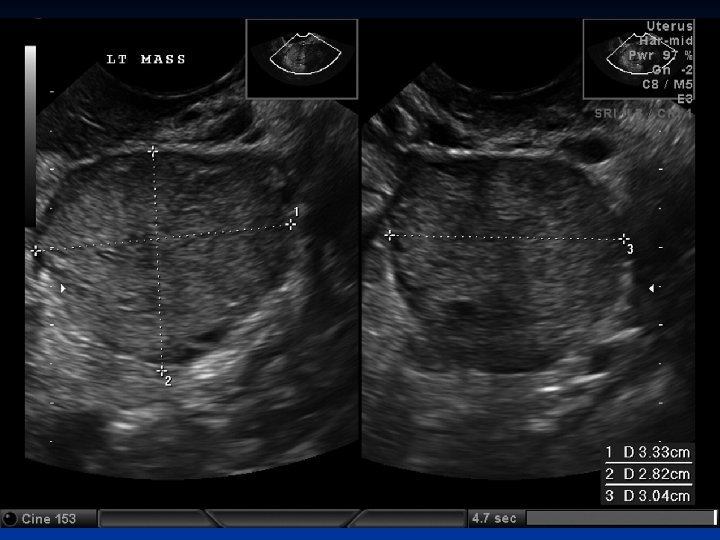

Leiomyoma Uteri n n n Benign neoplasm arising from smooth muscle cells in the uterine wall Pseudocapsule 20 -25% More commonly multiple Symptoms n n n Usually asymptomatic Metrorrhagia Menorrhagia Pain İnfertility

Leiomyoma Uteri n Clinical findings n n n Abnormal uterine bleeding 30% Pain Pressure effects n n Infertility n n n Intestinal obstruction Compress to ureters, bladder or rectum Pelvic venous compression Relationship is unknown 27 -40% of women with myomas are infertile Spontation abortion n 2 times more